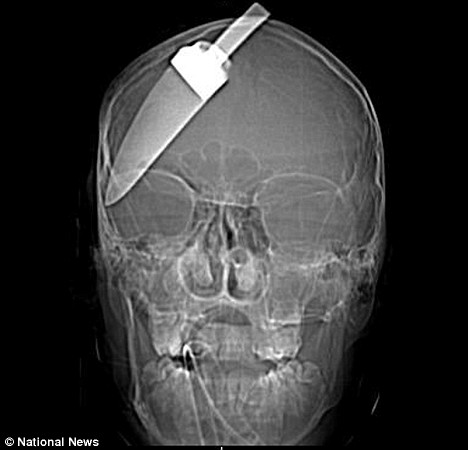

This harrowing picture shows an X-ray of a 15-year-old boy's skull after a five inch knife was plunged into his head.

Amazingly the teenager survived the stabbing and ten months on from the attack has enrolled in college.

He survived because he was rushed to hospital with the knife still sticking out of his head and doctors managed to operate in time.

X-rays released by police show how deep the knife penetrated, while still missing the boy's brain. Surgeons said if anyone had tried to take it out he would have died.